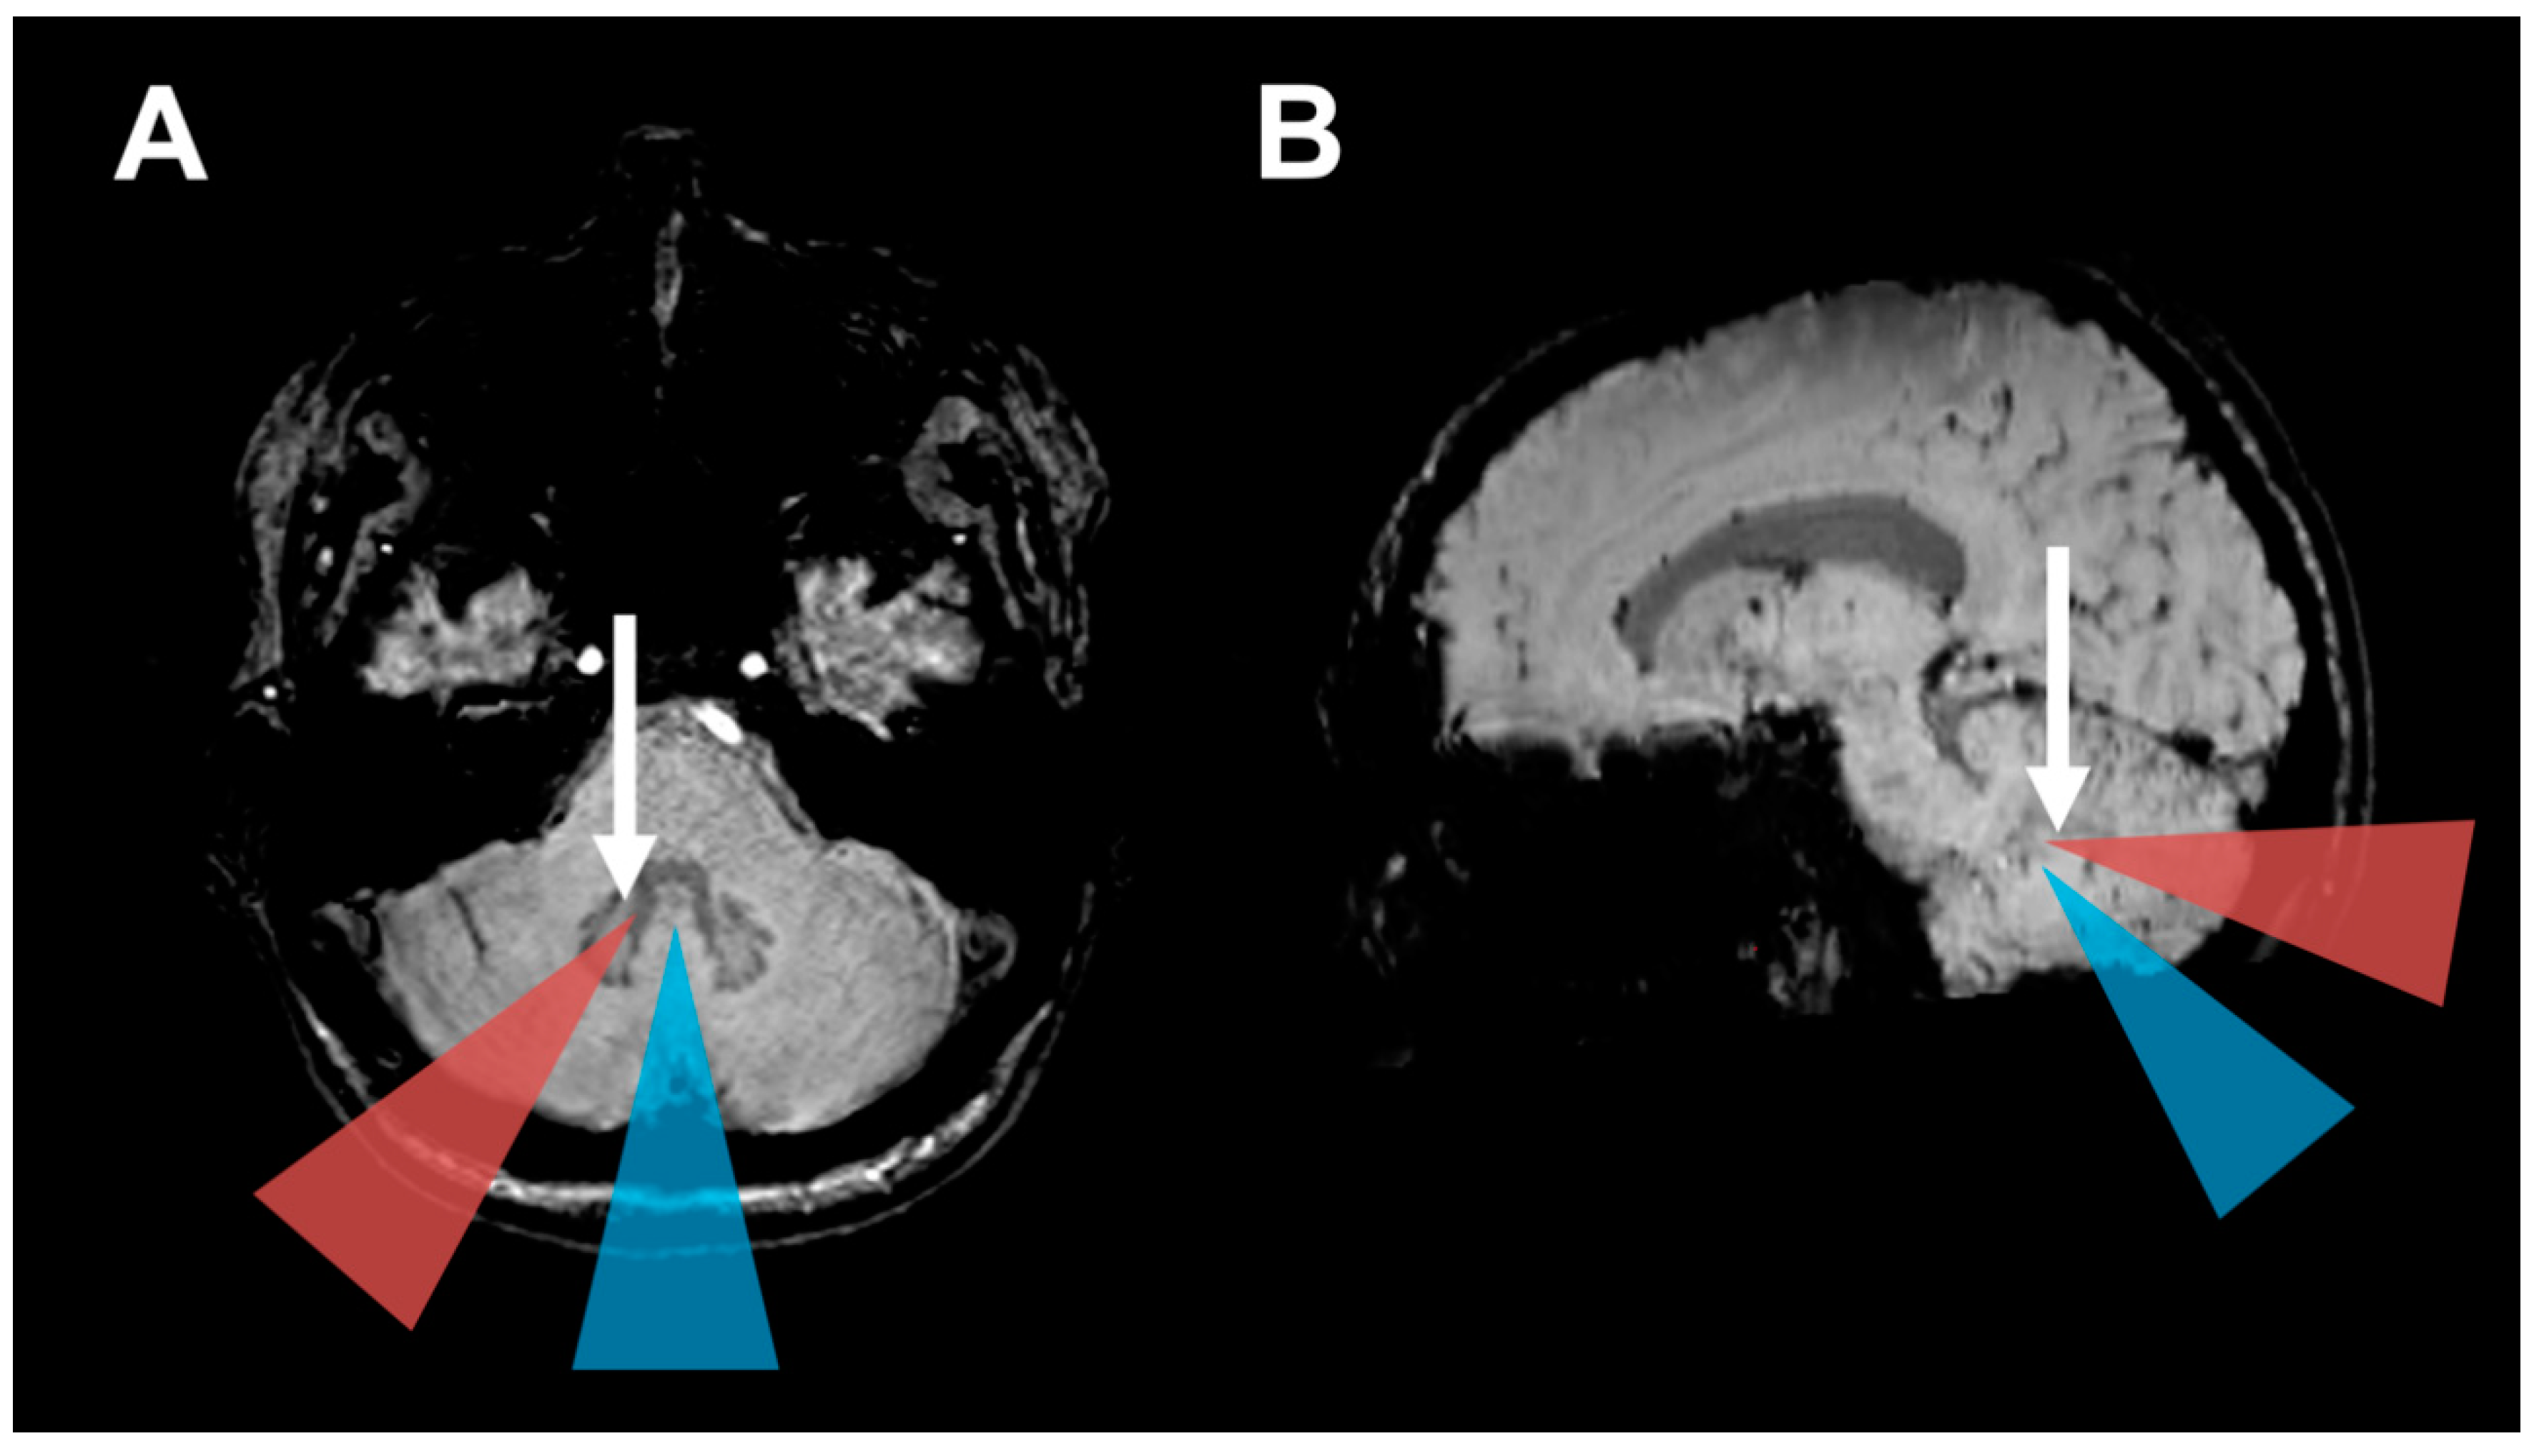

2.2. Surgical Approach and HOD Development

2.3. HOD-Patient Characteristics and Disease Pattern